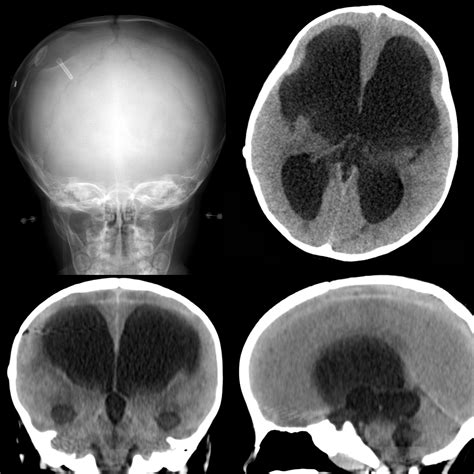

Hydrocephalus is a condition characterized by the accumulation of CSF in the brain, leading to increased intracranial pressure. This can cause a variety of symptoms, including headaches, nausea, and cognitive impairments. A VP shunt is a surgical solution that helps manage this condition by redirecting the excess fluid to the abdomen, where it can be absorbed naturally.

The VP shunt consists of several components:

• A catheter placed in the ventricles of the brain to drain the CSF.

• A valve that regulates the flow of CSF.

• A distal catheter that directs the fluid to the peritoneal cavity.